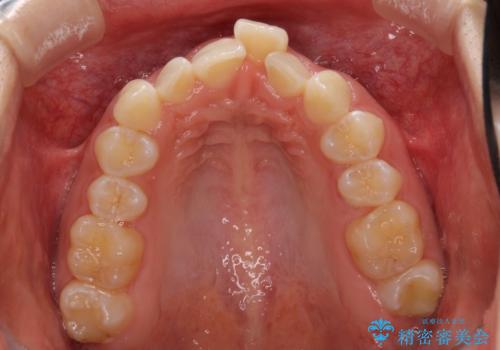

前歯のデコボコを治したい インビザライン矯正治療

- 前歯のデコボコ気になるとのことで来院された患者様です。

下顎骨が上顎骨に対して右側にシフトしており、さらに下顎が後方に位置しているため、非常に強い咬合力で食いしばっている状態でした。

上下顎ともに歯列全体の後方移動とIPR(歯と歯の間を削る)によってデコボコが解消するように設計し、インビザラインにより治療を行うこととしました。

強い咬合力による臼歯部の噛みにくさと、それに伴う歯の移動の鈍さに悩まされ、非常に長い期間を要することとなりました。

上下正中位置は、治療開始時よりは改善したものの、ここが限界であろうというところでのゴールとなりました。

下顎前歯の大半が隠れている状態ですが、左右への歯ぎしりはスムーズに行うことができ、就寝時には後戻り防止も兼ねて、食いしばり対策としてマウスピースの使用を継続するようお願いしております。